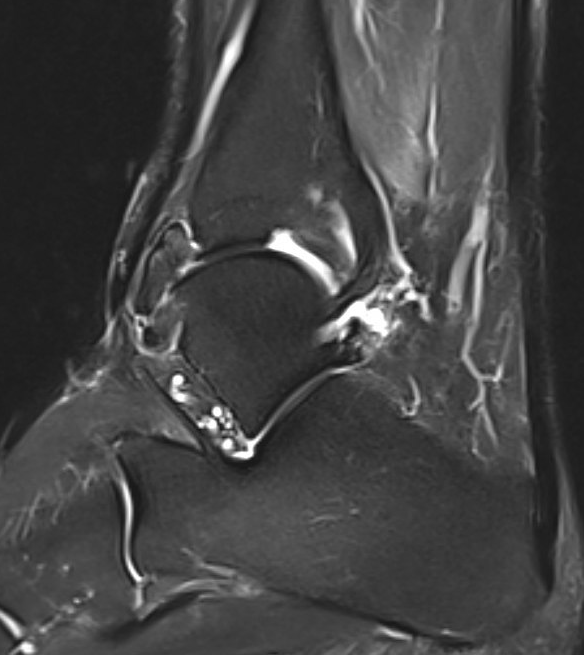

PVNS anterolateral gutter ankle

PVNS with ankle joint / talus erosion

Synovial osteochondromatosis

www.boneschool.com/synovial-osteochondromatosis

Chondroid metaplasia of synovium (synovial chondromatosis)

- form nodules of hyaline cartilage

- break free into joint

- lesions can mineralize or ossify (Synovial osteochondromatosis)